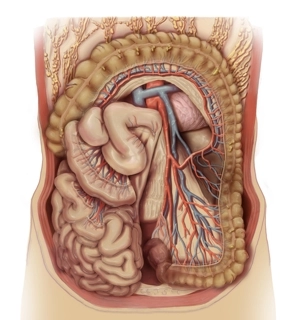

Relaciones topográficas

![Relaciones topográficas]()

Colon descendente, retroperitoneo y recto

- Trayecto del colon descendente de craneal a caudal con relación posicional estrecha al bazo (flexura cólica izquierda), bolsa omental (dorsomedial de la flexura cólica izquierda), riñón izquierdo y cola del páncreas (sección craneal del colon descendente)

- Trayecto de la raíz del mesocolon sigmoide desde la fosa ilíaca izquierda hacia medial, cruzando los vasos ilíacos comunes, el uréter y los vasos ováricos, o testiculares

- Trayecto del uréter sobre el músculo psoas, que cruza de lateral y craneal a caudal y medial.